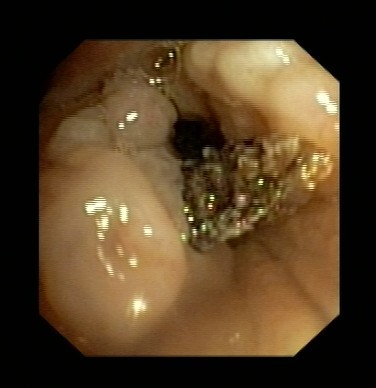

近日,呂先生有門診收入我呼吸科住院治療,全體醫(yī)護(hù)人員高度重視,認(rèn)真討論病情。我科吳主任仔細(xì)看過呂先生的CT片后,觀察到右下肺氣管內(nèi)異物,于是決定行支氣管鏡檢查。在氣管鏡室,吳主任給他做了支氣管鏡檢查,發(fā)現(xiàn)呂先生右下肺支氣管內(nèi)卡著一個黑黑的異物,由于時間太久,異物周圍已充血水腫,表面有膿苔及壞死物覆蓋,清除膿苔及壞死物后,可見異物被肉芽組織緊緊包埋。吳主任成功取出了呂先生氣管內(nèi)異物,并吸出了氣管內(nèi)膿性分泌物。呂先生咳嗽癥狀立刻改善,行氣管鏡檢查后第二天患者無咳嗽癥狀,順利出院。

圖表3取出異物后氣管周圍肉芽組織